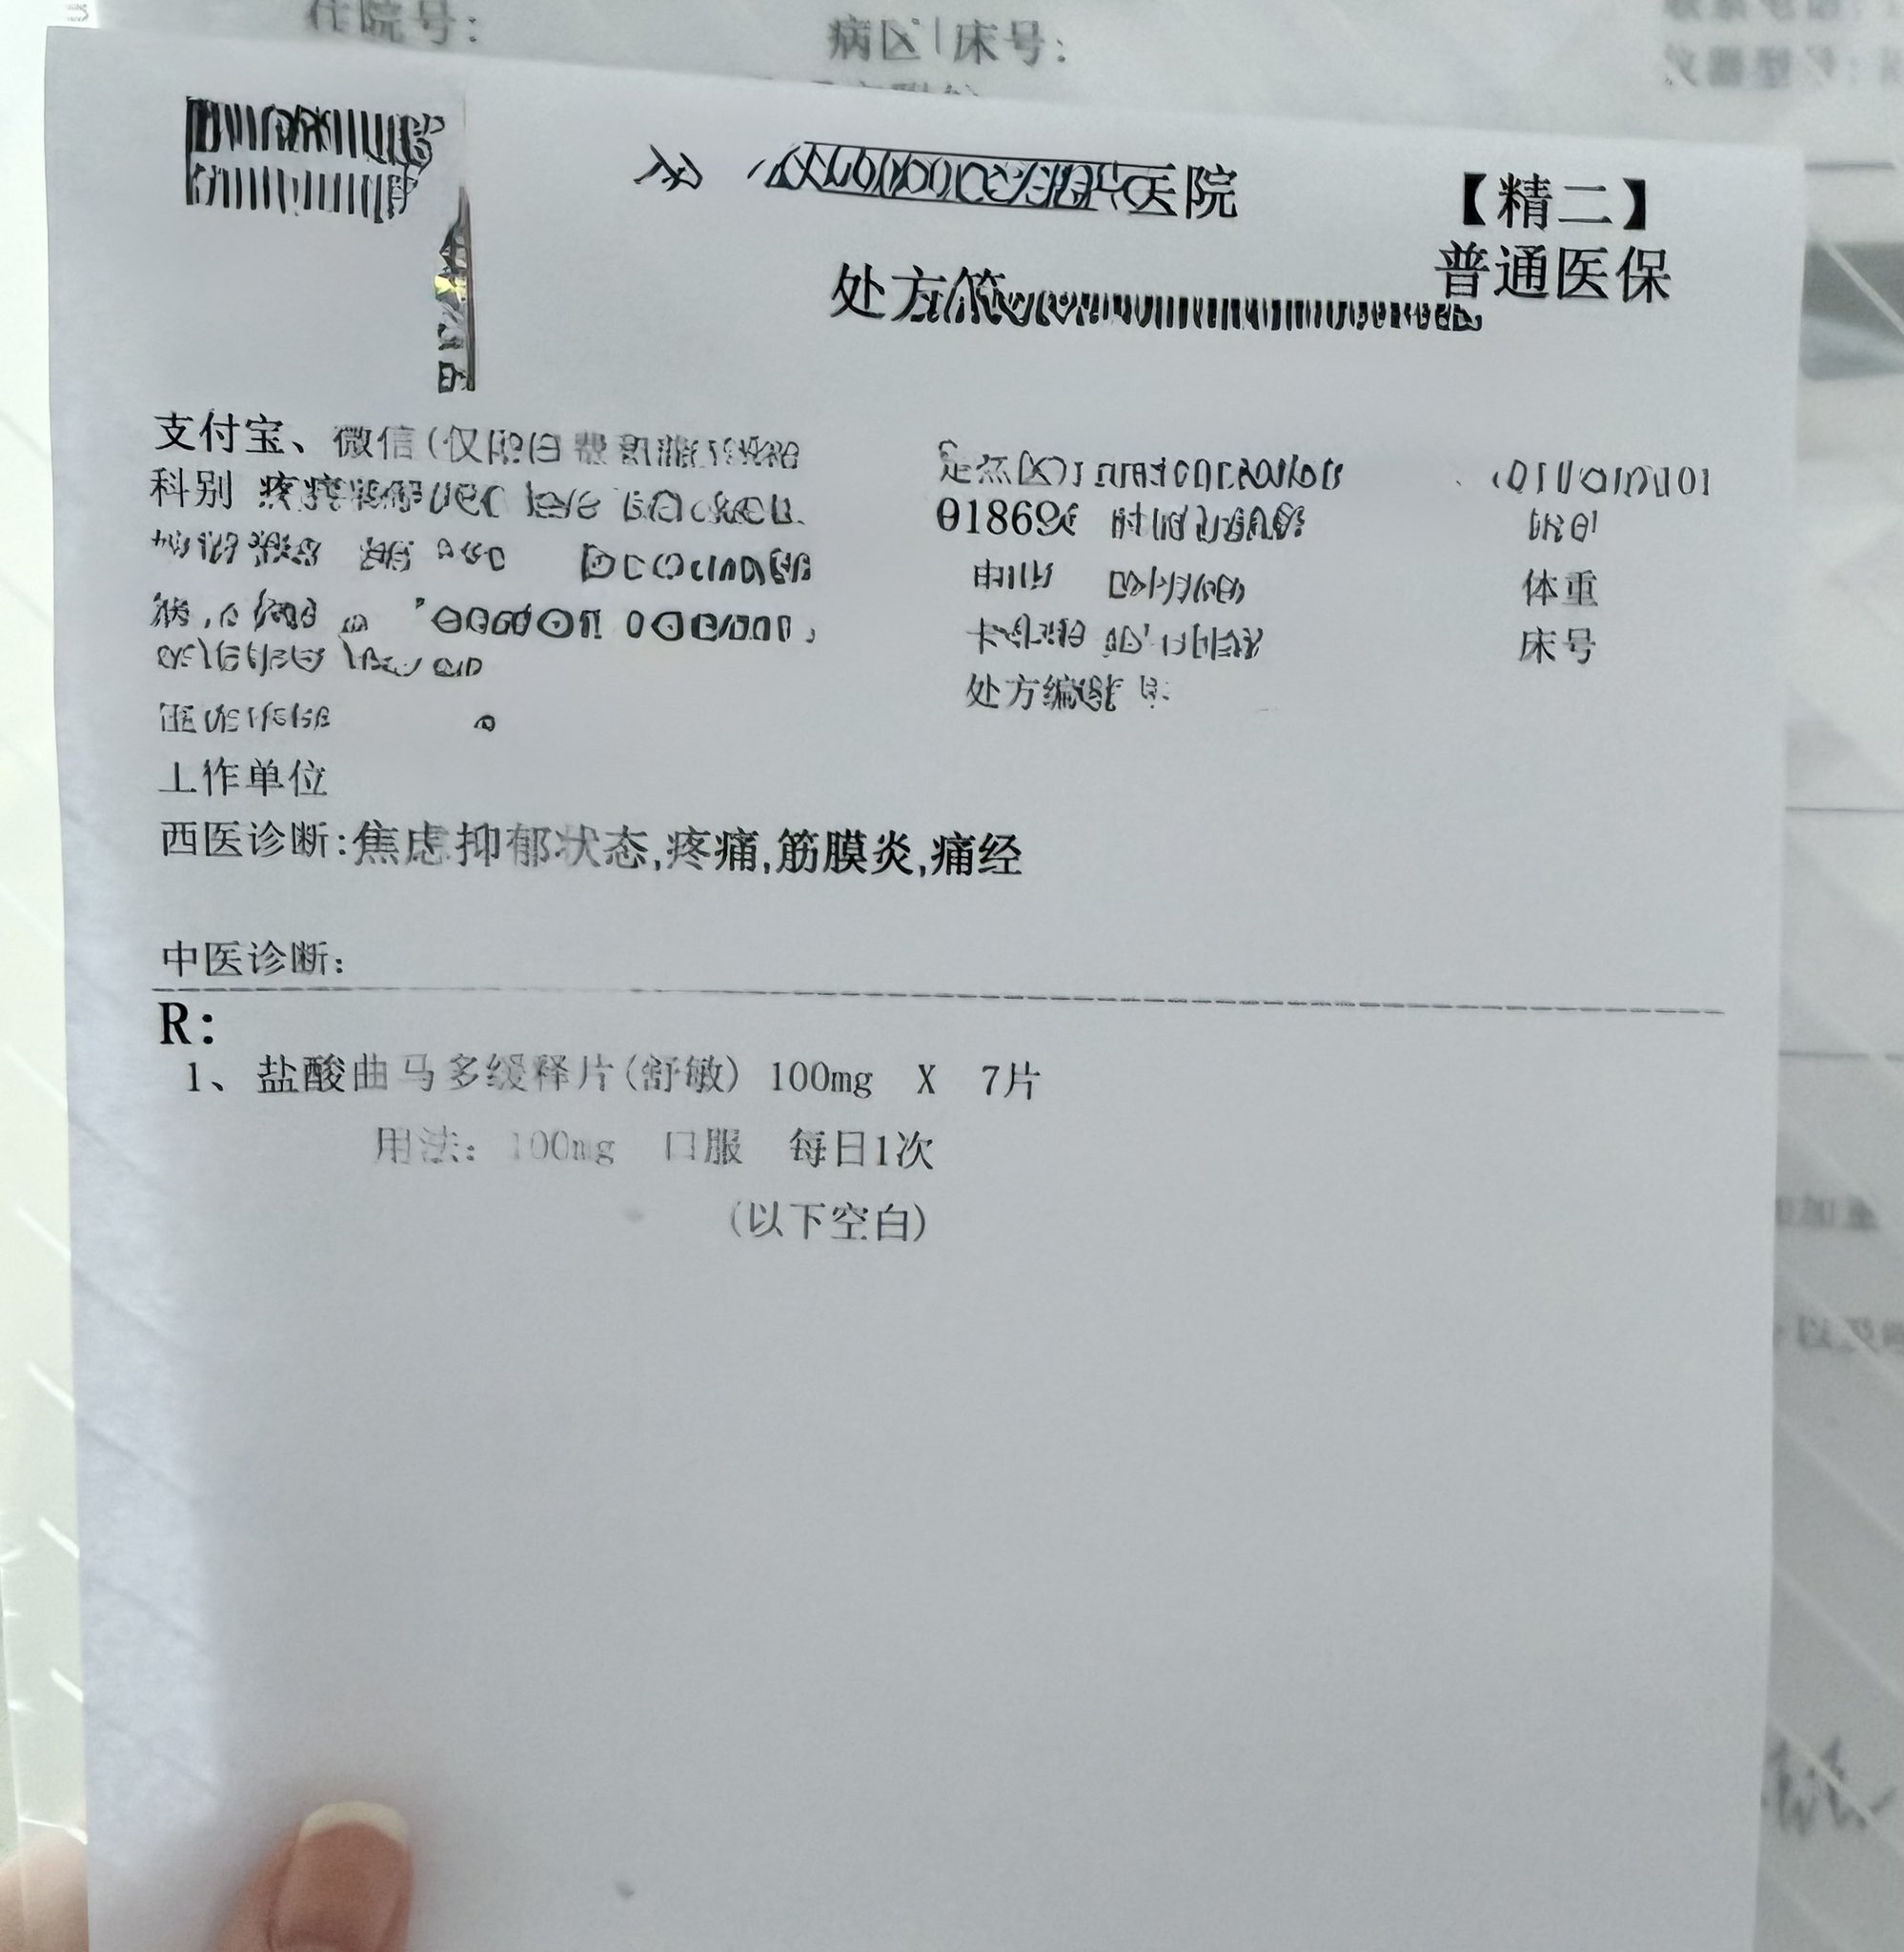

找值班医生护士开药,因为平常自己吃的没带过来,优先就考虑了曲马多(口服/注射),我说和我抗抑郁药cyp2d6冲突了

炽烈已极 @AnIncandescence我说不用那么强的也可以,医问加巴喷丁?我说弱了……于是目的达成,开了pr75

2026-03-22 15:58:58 UTC

虽然我吃这点可能没什么效果,但出院的时候说不定能开医嘱开处方甚至带药,处方有希望了!

炽烈已极 @AnIncandescence两年了,第一次正规途径吃到/开到普瑞…